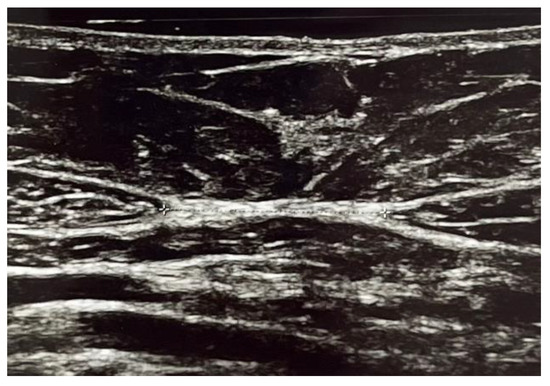

| DRA superior | 2.12 ± 0.98 | 2.1 ± 0.77 | 0.94 |

| DRA inferior | 0.98 ± 0.9 | 1.33 ± 0.87 | 0.009 |